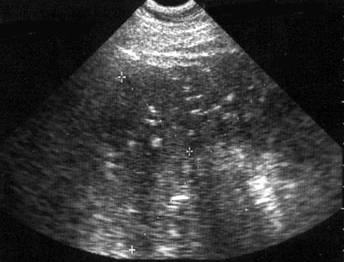

Ecografic, hematomul are aspectul oricarei colectii hematice, fiind hipoecogen sau chiar transsonic, situat cel mai frecvent subcapsular. El se dezvolta in special in portiunea ventrala a splinei, intre polul superior al rinichiului stang si splina.

In mod particular, hematoamele foarte recente pot avea ecogenitate relativ crescuta. In hematoamele subacute, hipoecogene, se vizualizeaza uneori mase cu ecogenitate variabila, date de cheaguri.

Hematomul intraparenchimatos poate fi unic sau multiplu, cu contur regulat sau anfractuos, cu amplificare acustica posterioara si nu prezinta, de obicei, imagine de perete.

Hematomul subcapsular apare ca o zona de colectie superficiala aplatizata (uneori, semilunara), cuprinsa intre parenchimul splenic si ecoul liniar al capsulei splenice decolate. Conturul parenchimului splenic poate fi regulat sau anfractuos, iar dimensiunile, foarte variabile.